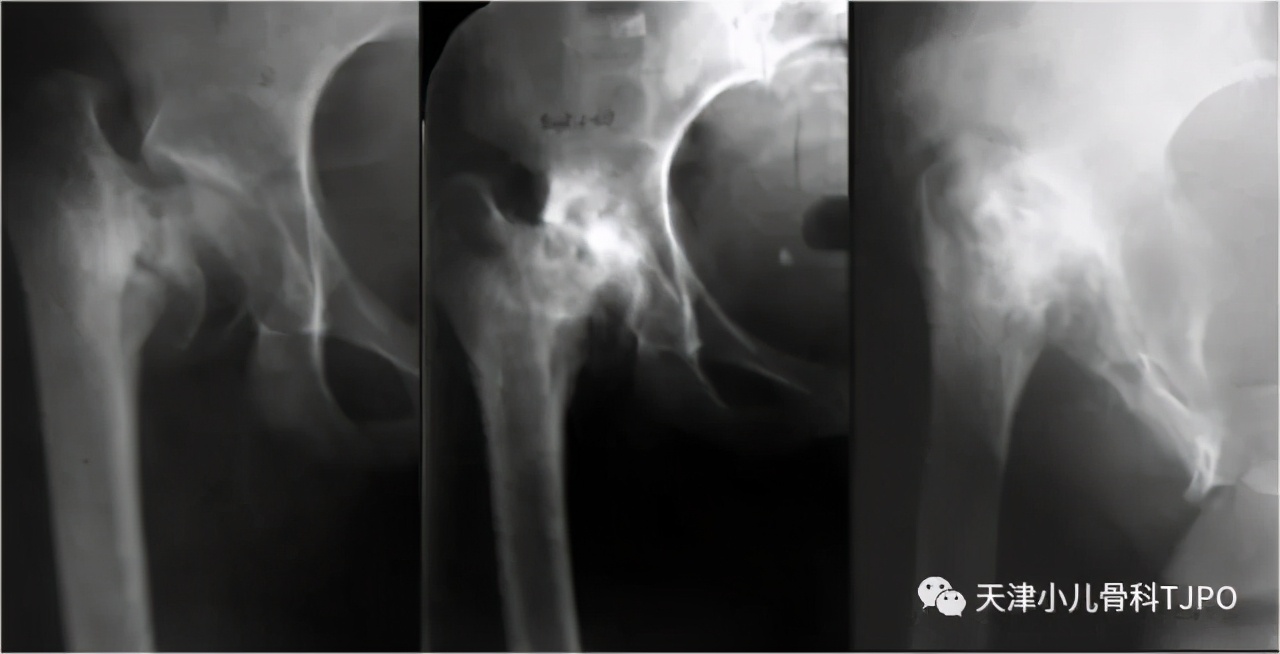

女孩,7岁时当地医院检查发现右侧先天性髋内翻畸形,测量HE角64°(图11a),行股骨近端外翻截骨术,采用150°钢板固定,术后截骨远端内移(图11b)。术后2年髋内翻复发(图11c)。行股骨近端外翻截骨翻修术,以140°php固定,截骨端为端-侧对合,固定后股骨近端形态更接近正常生物力学结构(图11d)。

图11